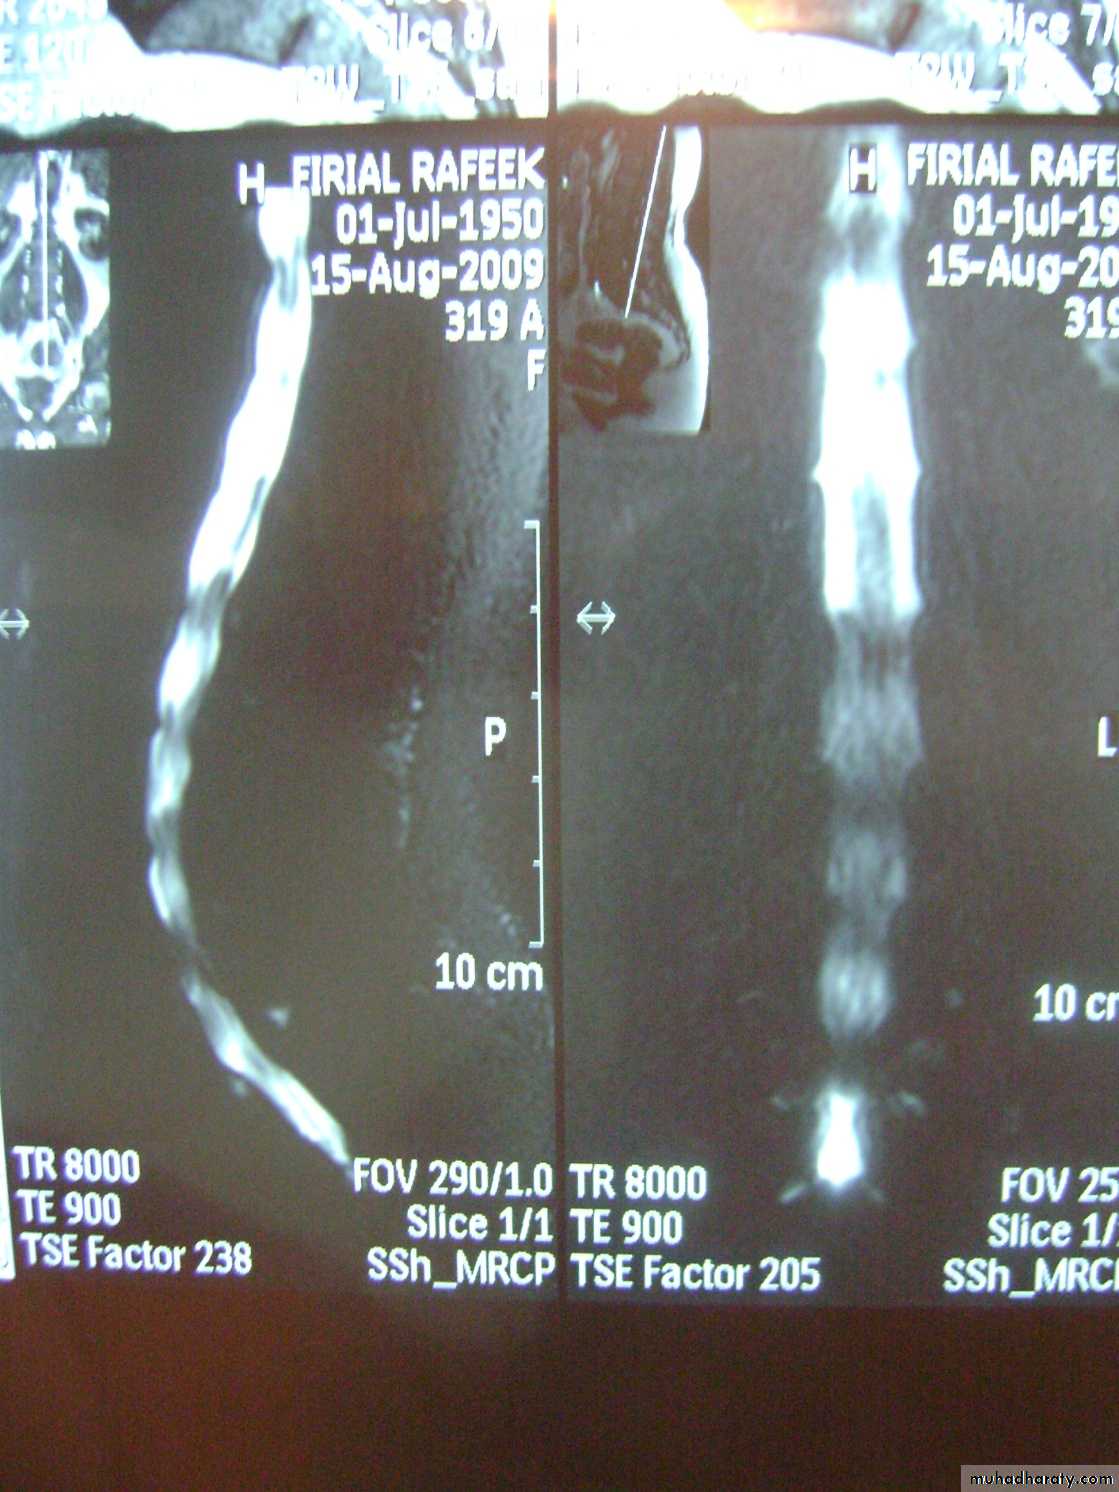

General examinations

ImagingPlain x-rays

AP and lateral views

Oblique views

PA view of S.I. Joint

Computed tomography (with mylography)

MR imaging

Radioisotope scanning

Discography and facet joint arthrography